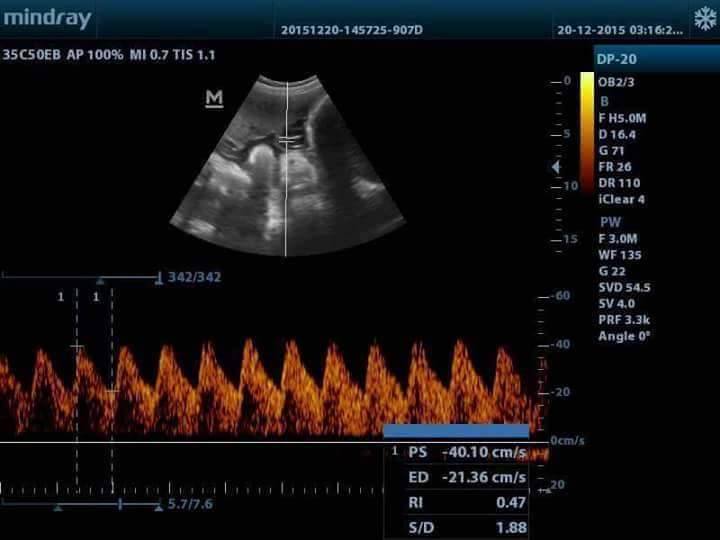

| Imaging Mode | 2D |

| Type of Transducer/ Probe | Convex |

| Doppler Mode | Pulse Wave |

| Monitor Size | 12.1 |

An ideal choice for an entry-level black & white ultrasound system, DP-20 comes equipped with a best-in-class combination of performance and affordability. With a new platform based on Intel’s powerful processor, DP-20 forms an integral part of Mindray’s new generation of portable B/W ultrasound systems equipped with the latest imaging technologies and convenient workflow options.

- iClear for Speckle Reduction Imaging, providing clear and sharp lesion contours.